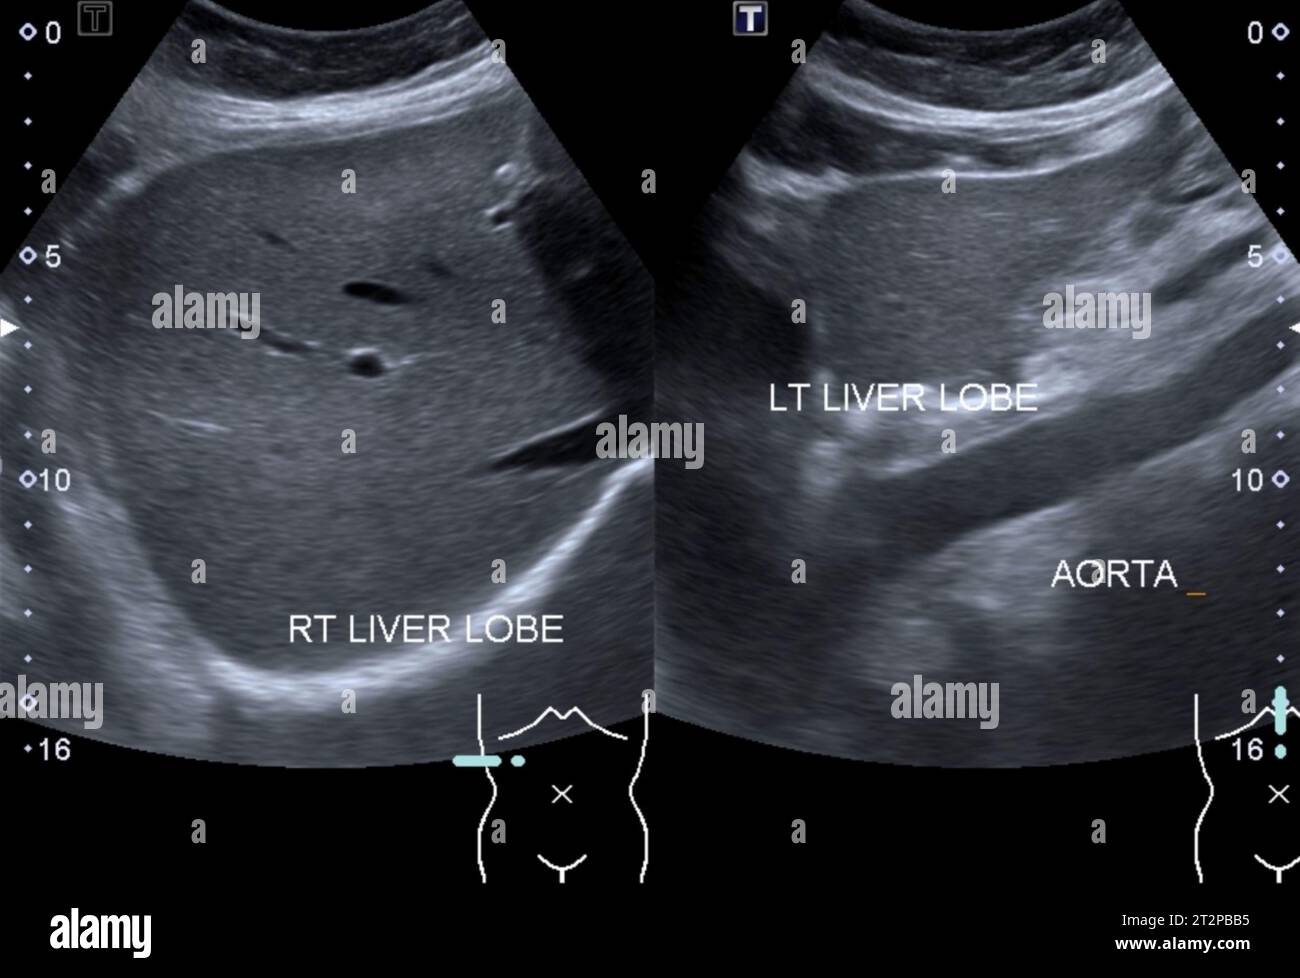

Preoperative liver ultrasound showing cirrhotic liver. Download

from www.researchgate.net